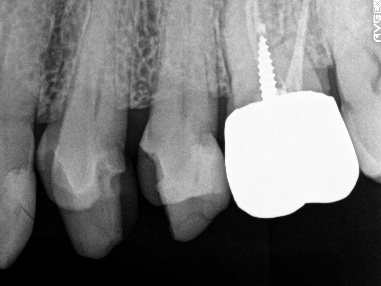

女性 Hさん 60代 (オールセラミック冠・インプラント)

主訴

右下のブリッジがゆらゆら動く。

治療内容

ブリッジの支台になっている奥の歯が、被せ物の中で虫歯になり、支台の役割を果たさず、前方の歯のみで支えられていました。前方の歯をそのままにして、後方の部分を切り離すと、そのまま取れてきました。中は、虫歯で歯根しか残っていない状況でした。この歯は、根管治療後、単独でオールセラミック冠を被せ、歯のないところにインプラントを埋入しました。

所感

今回の治療法には、次の3つの方法があります。

(1)虫歯になっていた歯の根管治療をし、土台を入れ、また再びブリッジにする。しかし、虫歯になっていたほうの歯は、ブリッジの支台として使うには、心もとなく長持ちしない可能性が高く、今度問題が生じたときには抜歯になる。

(2)虫歯になっていた歯に、単独で被せ物をし、歯のないところに1本だけの部分入れ歯を入れる。取り外しの入れ歯なので、自分の歯のような感覚で噛むことはできない。この方法も歯のない部分の負担を欠損の両側の歯に負担してもらうため、長持ちしない可能性が高い。

(3)虫歯になっていた歯に、単独で被せ物をし、歯のないところにインプラントを埋入する。欠損している部分の負担を前後の歯に負担させないので、歯を守ることができる。また、自分の歯と同じ感覚で食事をすることができる。

患者さんは、3つ目の方法を選択されました。一番長持ちし、これ以上歯を失わないためには、最良の方法だと考えます。

オールセラミック冠(失活歯):¥104,500(税込)

インプラント:¥363,000(税込)

合計:¥467,500(税込)

Before

冠の中で大きな虫歯になり支台の役割を果たしていませんでした。

【インプラント埋入前】

冠はブリッジを切断しただけで取れてきました。軟化象牙質を取り除いたところ、歯根しか残っていない状況で保存できるかどうかのぎりぎりのところでした。

After